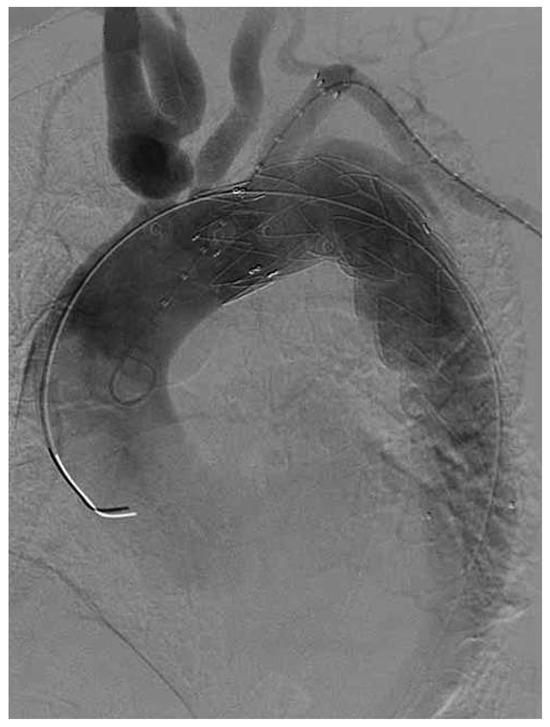

Endovascular Treatment of a Complex Type B Aortic Dissection

Case report